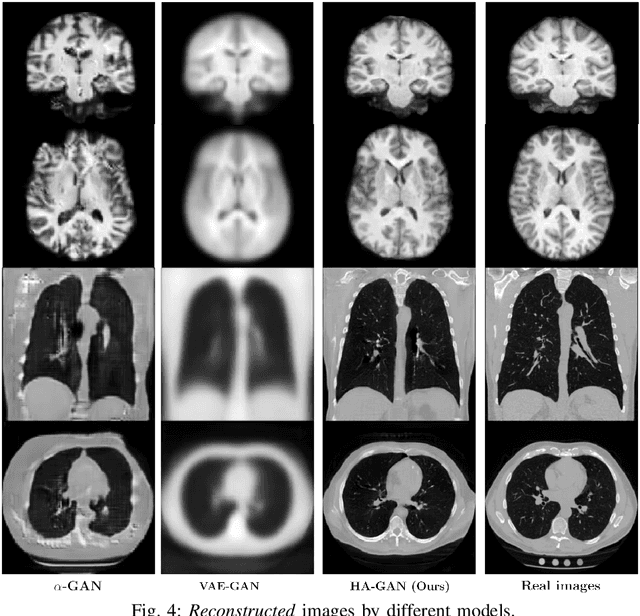

Abstract:Generative Adversarial Networks (GAN) have many potential medical imaging applications, including data augmentation, domain adaptation, and model explanation. Due to the limited embedded memory of Graphical Processing Units (GPUs), most current 3D GAN models are trained on low-resolution medical images. In this work, we propose a novel end-to-end GAN architecture that can generate high-resolution 3D images. We achieve this goal by separating training and inference. During training, we adopt a hierarchical structure that simultaneously generates a low-resolution version of the image and a randomly selected sub-volume of the high-resolution image. The hierarchical design has two advantages: First, the memory demand for training on high-resolution images is amortized among subvolumes. Furthermore, anchoring the high-resolution subvolumes to a single low-resolution image ensures anatomical consistency between subvolumes. During inference, our model can directly generate full high-resolution images. We also incorporate an encoder with a similar hierarchical structure into the model to extract features from the images. Experiments on 3D thorax CT and brain MRI demonstrate that our approach outperforms state of the art in image generation, image reconstruction, and clinical-relevant variables prediction.